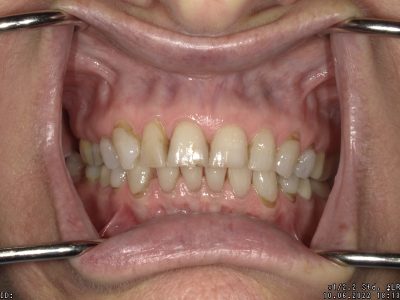

A case done with a combination of Crowns and Veneers on her upper anterior teeth.